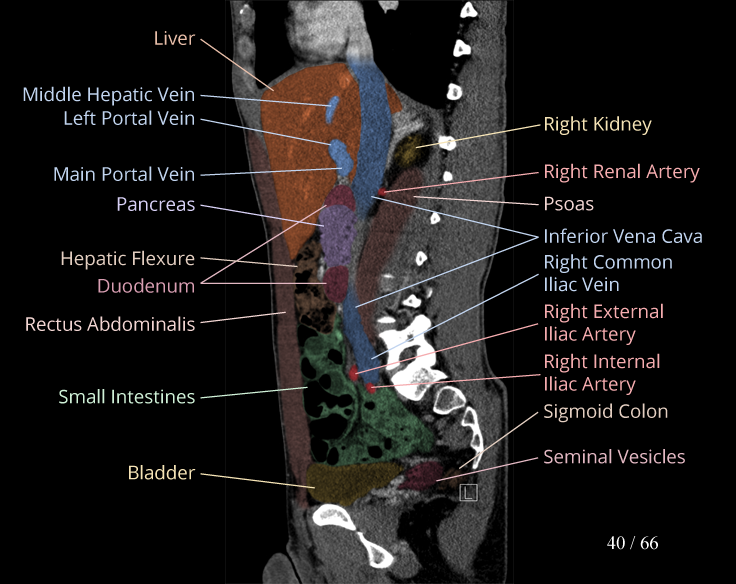

Body

Covers abdominal CT anatomy.